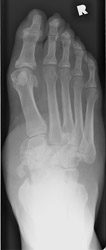

Charcot Joint: AP -Charcot Joint: Lateral - Disorganization of Chopart jointNEUROPATHIC JOINT DISEASE (CHARCOT JOINT) articular degeneration secondary to weight-bearing trauma and neurovascular changes on sensory deficient joint, resulting in bony resorption and formation.

Bilateral metatarsophalangeal joint involvement is common, especially among diabetics. The second tarso metatarsal joint is a frequent site for early subluxations. Mono- or polyarticular interphalangeal joint or midfoot presentations may also occur.

Osteophytes, joint effusions, and soft tissue swelling are among the common early findings. Later in the disease process, acute fractures, dislocations, and subluxations may occur. Subluxations at the tarso metatarsal joints may mimic Lisfranc fracture/subluxations. Frequent fractures include subchondral fractures of the second metatarsal head, and avulsion fractures of the posterior calcaneal tubercle. Tapering osteolysis ("sucked candy" or "pencil-pointing"), bony fragmentation with well defined margins, and fusions with or without pseudoarthroses are other signs of progression.